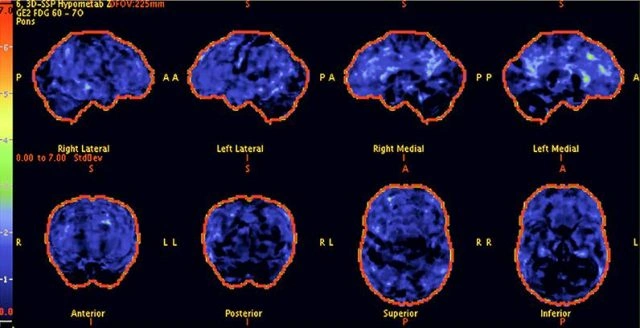

Above: The patient's PET scan after CureFight treatment shows improvement, with cognitive abilities greatly enhanced as the scan approaches that of a normal brain.